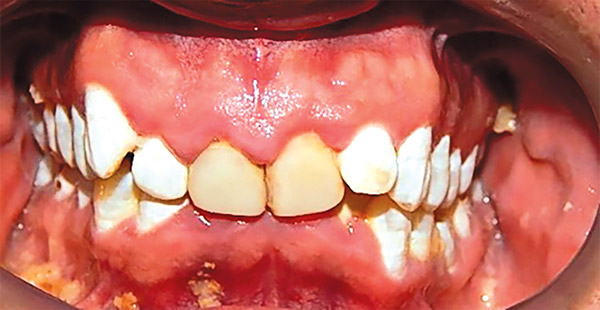

En las fotografías intraorales se muestra la fluorosis dental Tf4 y Tf7, las relaciones molares clase II molar y canina bilateral (Figura 3 y 4), el apiñamiento severo superior e inferior, con el órgano dental 35 en infraoclusión. El overbite aumentado y las líneas medias dentales no son coincidentes (Figura 5), las formas de arco superior e inferior son cuadradas (Figura 6 y 7).

Figura 3. Intraoral derecha.

Figura 5. Frente.